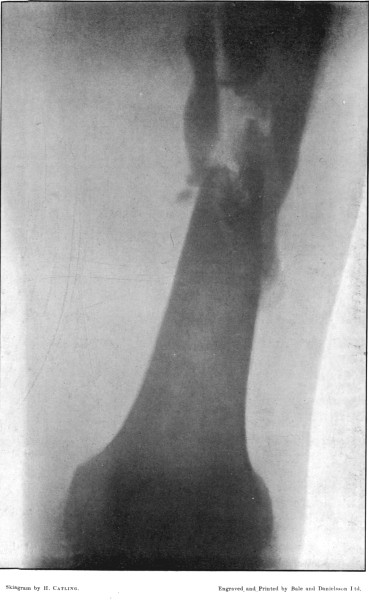

4. Comminuted Fracture of Shaft of Humerus180

5. Comminuted Fracture of Humerus accompanied by an Explosive Exit182